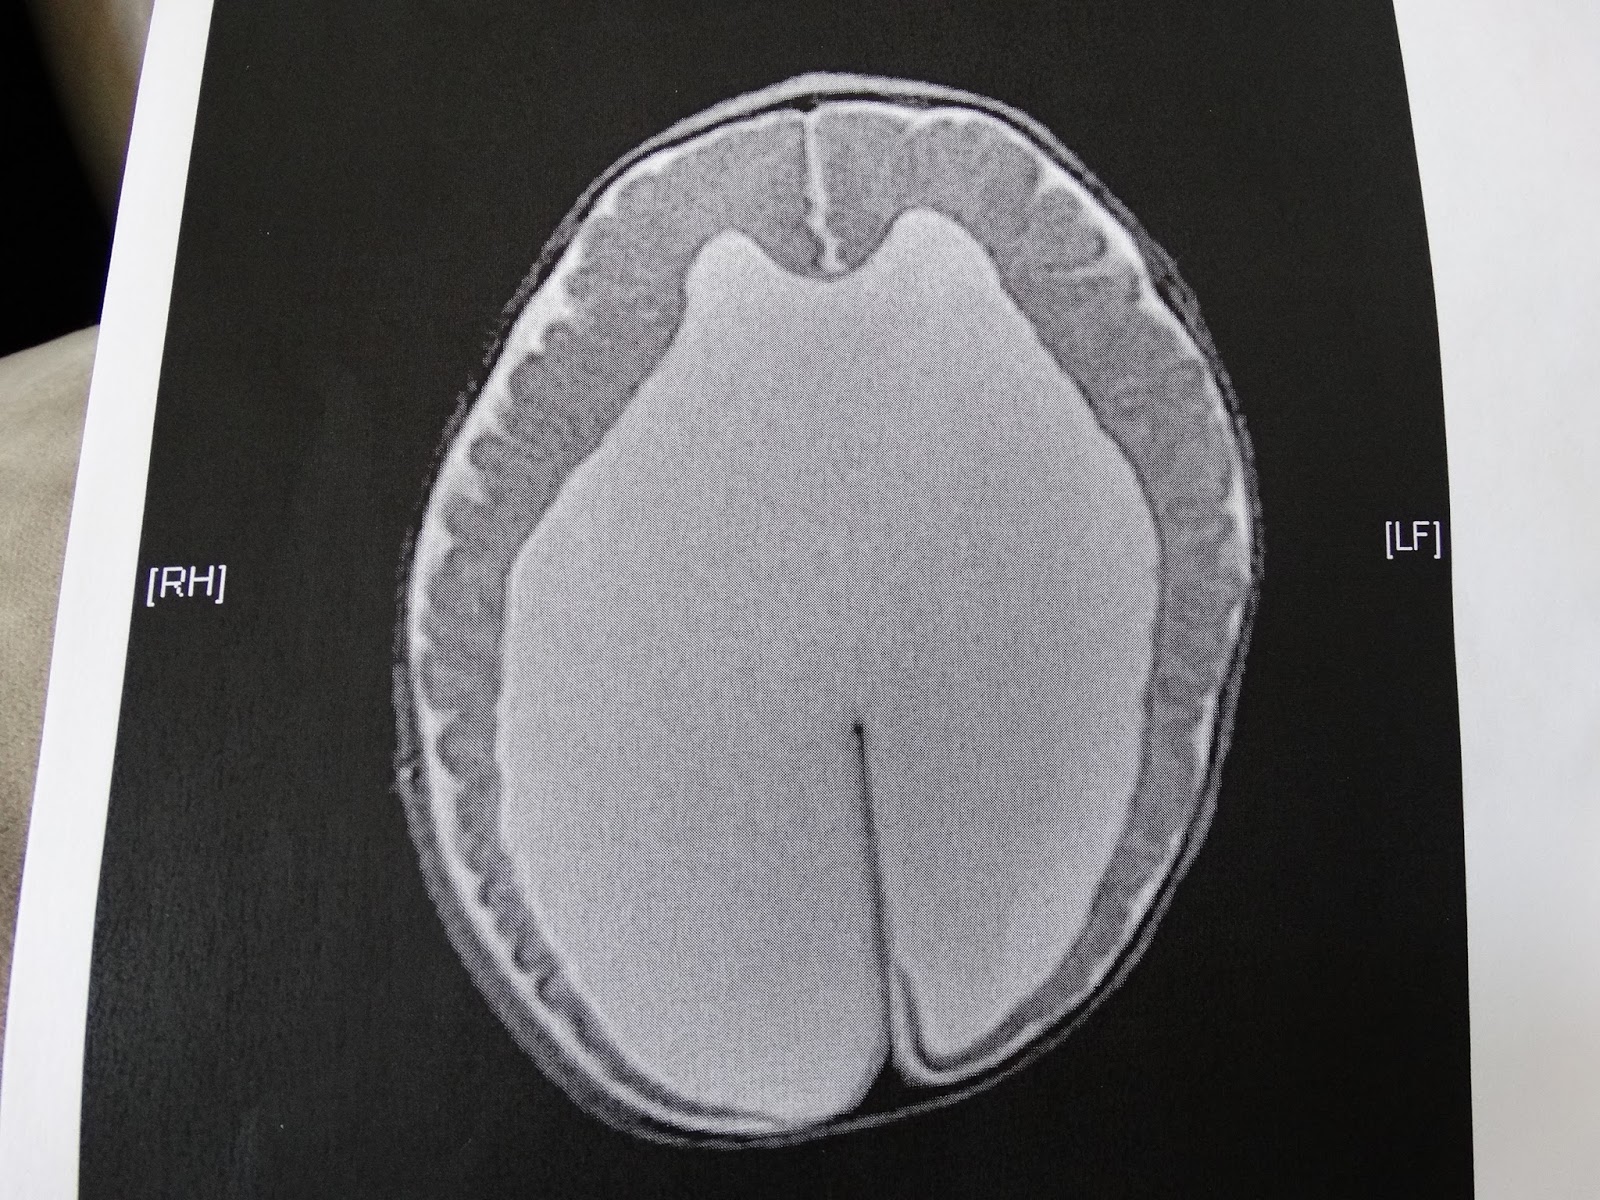

takeaway from the appointment is the diagnosis of Cortical/Cerebral Visual

Impairment, or CVI. Just like the

Whew, sorry for the rambling! Anyway, CVI basically means the eyes work

just fine; it’s the part of the brain that processes vision that is

impaired. It’s a complicated diagnosis